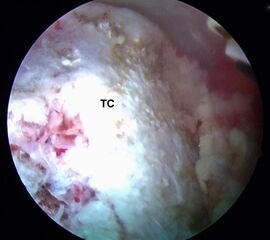

Abbildungen 5-8, Video 2

Anschließend wird die FHL-Sehne angeschlungen. Hierzu wird die Fadenschlaufe über das posteromediale Portal mit einer Fadenzange oder einem gebogenen Klemmchen um die FHL-Sehne geführt und anschließend wieder aus dem Portal herausgezogen. Nach Durchfädeln der freien Fadenenden durch die Schlaufe wird die Schlinge festangezogen. Die Technik wird in Video 2 demonstriert.

Zur Vollansicht bitte die Bilder anklicken. Fotos: M. Galla.